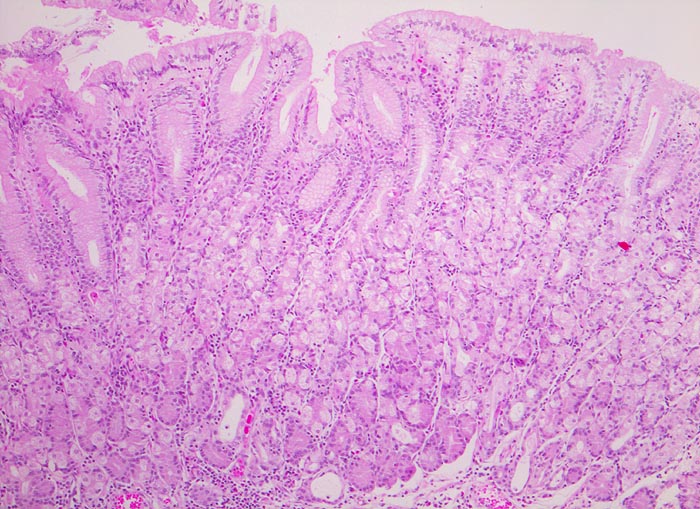

Die ersten beiden Typen entsprechen histologisch meist einem intestinalen Typ nach Lauren (> 1342). Diese Tumoren sind scharf begrenzt, bilden tubuläre oder papilläre Strukturen wie die Dickdarmkarzinome, sind meist assoziiert mit bekannten umweltbedingten Risikofaktoren und haben eine bessere Prognose.

Adenokarzinome können tubuläre, papilläre, muzinöse, siegelringzellige und undifferenzierte Anteile aufweisen, wobei die beiden letzteren besonders aggressive Tumoren darstellen.

• Ein Grossteil des Tumorinfiltrats besteht aus einzeln oder in kleinen Gruppen liegenden Zellen mit intrazytoplasmatischen Schleimvakuolen, die teilweise den Kern verdrängen (Siegelringzellen): diffuser Typ des Magenkarzinoms nach Lauren.

• Nur vereinzelt Drüsenbildung.